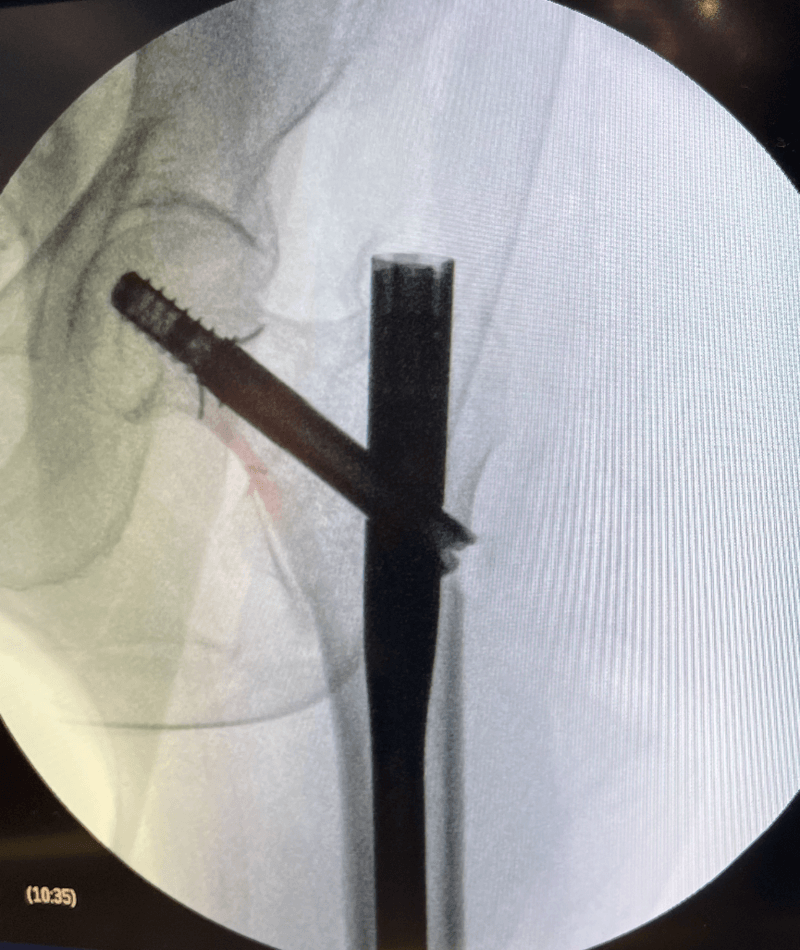

Intertrochanteric / Subtrochanteric / Femoral Shaft

- Trochanteric Fixation Nails

- Antegrade/ Retrograde Femoral Nails